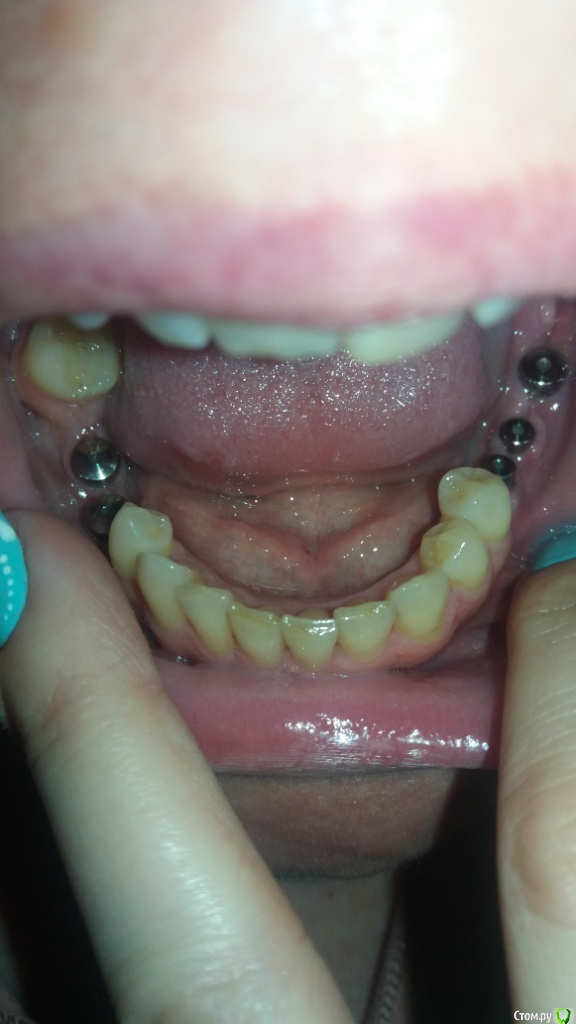

Oksana-p Опубликовано 23 мая, 2016 Автор Поделиться Опубликовано 23 мая, 2016 Ну 8й не проблема. Что касается остального, то нужны новые снимки и желательно внутриротовые фото Если подойдет -то вот фото на телефон (извиняюсь за качество, вечером попрошу кого-нибудь сфотографировать) Ссылка на комментарий

Oksana-p Опубликовано 24 мая, 2016 Автор Поделиться Опубликовано 24 мая, 2016 Еще сфоткала. На снимок ехать 200 км. Мне хирург почему-то его после установки формирователей даже не сделал. Как назло, и десна возле последнего импланта слева болит при надавливании и ноет. Полощу хлоргексидином. Позвонил хирург, сказал, что у меня все "в норме", что у меня уже лучше ничего не получится, что слишком тонкая кость, типа - скажите спасибо "хоть так поставили". Ссылка на комментарий

Oksana-p Опубликовано 15 июня, 2016 Автор Поделиться Опубликовано 15 июня, 2016 Вот такая ситуация сейчас..... Ссылка на комментарий